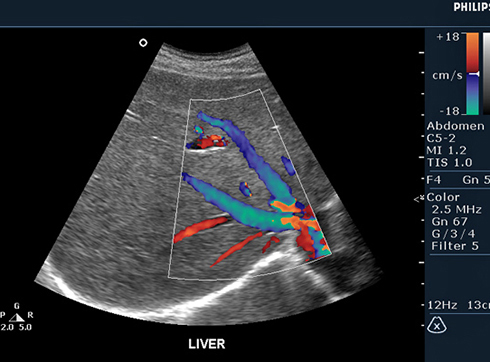

ЦДК сосудов почек: что это и как проводится